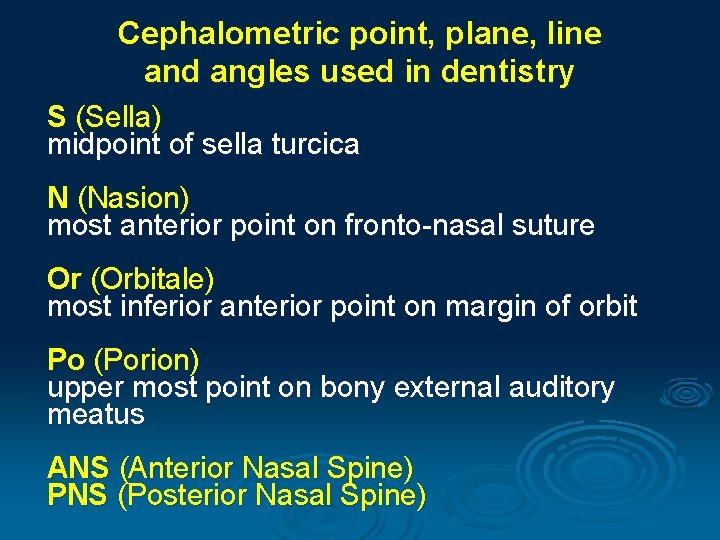

Cephalometric point, plane, line and angles used in dentistry S (Sella) midpoint of sella turcica N (Nasion) most anterior point on fronto-nasal suture Or (Orbitale) most inferior anterior point on margin of orbit Po (Porion) upper most point on bony external auditory meatus ANS (Anterior Nasal Spine) PNS (Posterior Nasal Spine)